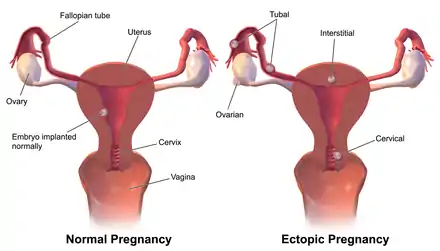

Ectopic pregnancy

Occasionally the embryo implants outside of the uterus, creating an ectopic pregnancy. Most ectopic pregnancies occur in the fallopian tube, and are commonly known as tubal pregnancies.[23]

The fallopian tube allows the passage of an egg from the ovary to the uterus. When an oocyte is developing in an ovary, it is surrounded by a spherical collection of cells known as an ovarian follicle. Just before ovulation, the primary oocyte completes meiosis I to form the first polar body and a secondary oocyte, which is arrested in metaphase of meiosis II.

At the time of ovulation in the menstrual cycle, the secondary oocyte is released from the ovary. The follicle and the ovary's wall rupture, allowing the secondary oocyte to escape. The secondary oocyte is caught by the fimbriated end of the fallopian tube and travels to the ampulla. Here, the egg is able to become fertilized with sperm. The ampulla is typically where the sperm are met and fertilization occurs; meiosis II is promptly completed. After fertilization, the ovum is now called a zygote and travels toward the uterus with the aid of the hairlike cilia and the activity of the muscle of the fallopian tube. The early embryo requires critical development in the fallopian tube.[10] After about five days, the new embryo enters the uterine cavity and, on about the sixth day, begins to implant on the wall of the uterus.

The release of an oocyte does not alternate between the two ovaries and seems to be random. After removal of an ovary, the remaining one produces an egg every month.[19]